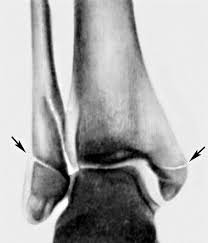

СКЛАДНИЙ СУГЛОБ (ЯК ВИЛКА). Є ВСІ ПЕРЕДУМОВИ ДЛЯ РОЗТЯГНЕННЯ ЗВ'ЯЗОК І ЗМІЩЕННЯ КІСТОК. РОЗПІЗНАЙТЕ СУГЛОБ.

варіанти відповідей

СУГЛОБ УТВОРЕНИЙ СУГЛОБОВИМИ ПОВЕРХНЯМИ ЛАТЕРАЛЬНОЇ І МЕДІАЛЬНОЇ КІСТОЧКИ ТА ТІЛОМ ТАРАННОЇ КІСТКИ. РУХИ НАВКОЛО ФРОНТАЛЬНОЇ ОСІ. ЧАСТО - РОЗТЯЖІННЯ, ВИВИХИ, РОЗРИВИ, ПЕРЕЛОМИ. РОЗПІЗНАЙТЕ СУГЛОБ.

КОЛІННИЙ С.

ГОМІЛКОВО-СТОПНИЙ С.

КУЛЬШОВИЙ С.

ЛІКТЬОВИЙ С.

ПЛЕЧОВИЙ С.

ПРОМЕНЕВО-ЗАП'ЯСТКОВИЙ С.